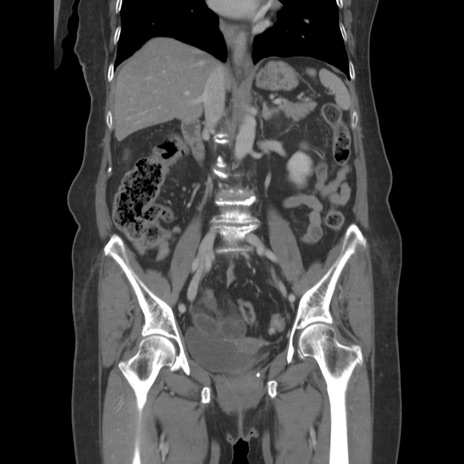

症例19(冠状断像)

【症例】80歳代女性

【主訴】下腹部痛

【現病歴】約8時間前より下腹部痛の出現あり、救急外来受診。

【既往歴】両側付属器切除

【身体所見】意識清明、下腹部正中に手術痕あり、その部位に一致して圧痛と反跳痛あり。腸蠕動音は亢進。

【データ】WBC 9300、CRP 0.15